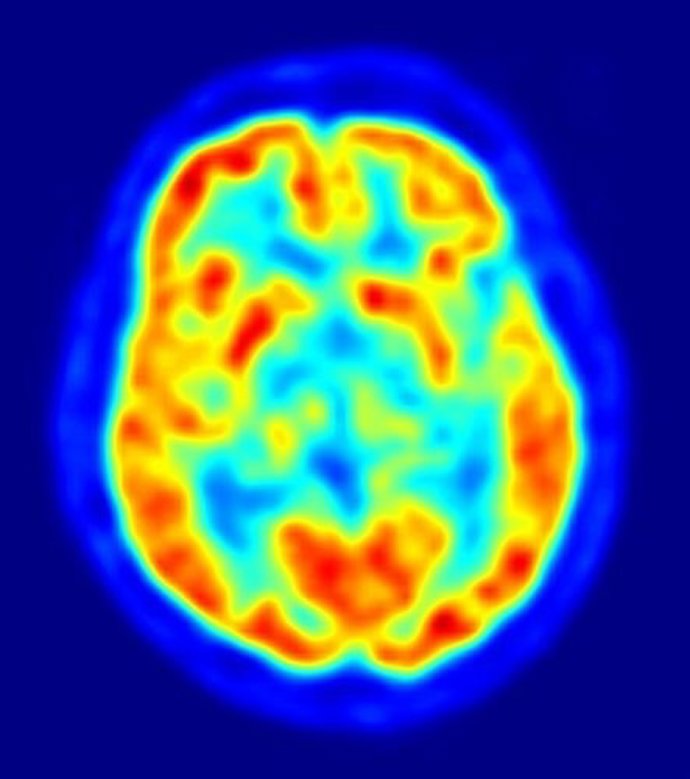

Imagen De Un Cerebro

Cuando los niños son expuestos a la violencia familiar, sus cerebros comienzan a incrementar el procesamiento de las posibles fuentes de amenaza, según informa un nuevo estudio, publicado en la revista 'Current Biology', en el que los investigadores han observado un patrón de actividad cerebral en estos niños similar al observado anteriormente en soldados expuestos a combate. Este nuevo estudio es el primero en aplicar la imagen funcional del cerebro para explorar el impacto del abuso físico o la violencia doméstica en el desarrollo emocional de los niños.

El nuevo estudio señala cómo los cerebros de los niños con exposición documentada a la violencia en el hogar responden a los rostros que muestran enfado: los niños con antecedentes de abuso muestran una mayor actividad en la ínsula anterior del cerebro y la amígdala, regiones que participan en la detección de amenazas y anticipan el dolor.

Según los investigadores, los cambios no reflejan daño cerebral; por el contrario, los patrones representan cómo se adapta el cerebro a un entorno difícil y peligroso. Sin embargo, esos cambios pueden producir posteriormente una mayor vulnerabilidad al estrés.